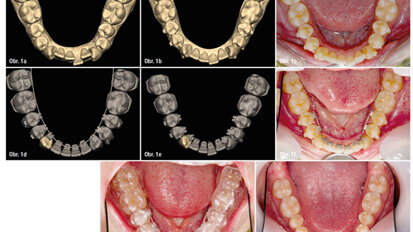

Hybridní terapie alignery